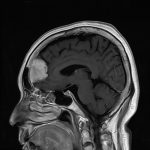

術中写真

摘出 前